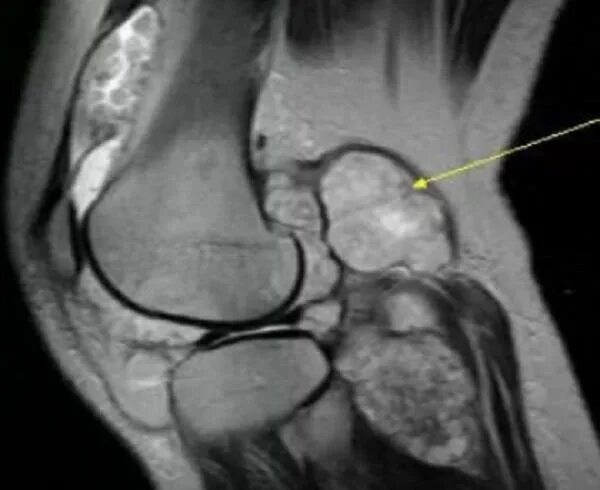

Саркома мрт